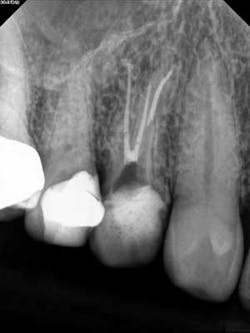

- Endo has never been one of my strong points in dentistry. I have found that spending time with my referring endodontist has allowed me to obtain a better understanding and acquire more honed in clinical skills. In addition to this, we also converse regularly on cases that I refer. Treatment plans are solidified with the use of newer technology because the diagnosis of pathology is more accurate. For example, we have found the 3-D cone beam to be quite advantageous to assess why a root canal is failing or noting the presence of that tricky third canal on a premolar or bifurcated canal on the molar.

3 canals! Courtesy of Dr. Joe Petrino, DDS